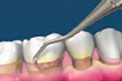

根管治疗,俗称“杀神经”,是现有治疗牙髓炎和根尖周炎的优选方法。显微根管治疗通过去除根管内感染物、充填根管、封闭冠部等系列治疗方式,阻断根尖周病变与扩撒,并推进炎症愈合。可谓是一项“救牙工程”,是目前保存病牙常用的治疗方法。

显微根管治疗能达到的效果